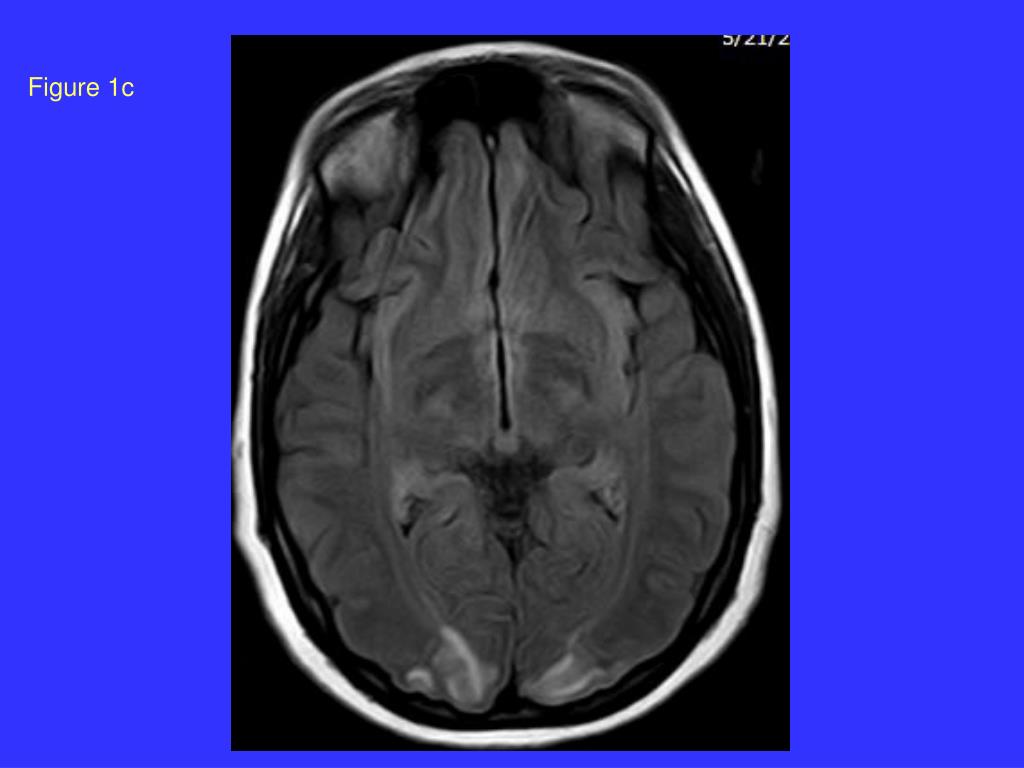

21. Figure 1b

20. Posterior reversible encephalopathy syndrome (PRES): Occipital-parietal cortical and white matter changes in pre-eclampsia. Is this due to capillary damage in the brain? Port JD, Beauchamp RadioGraphics 1998; 18:353-36ı ‘